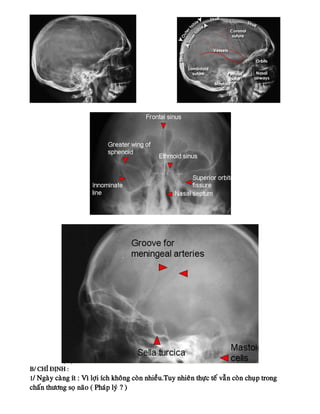

B/ CHÆ ÑÒNH :

1/ Ngaøy caøng ít : Vì lôïi ích khoâng coøn nhieàu.Tuy nhieân thöïc teá vaãn coøn chuïp trong

chaán thöông soï naõo ( Phaùp lyù ? )